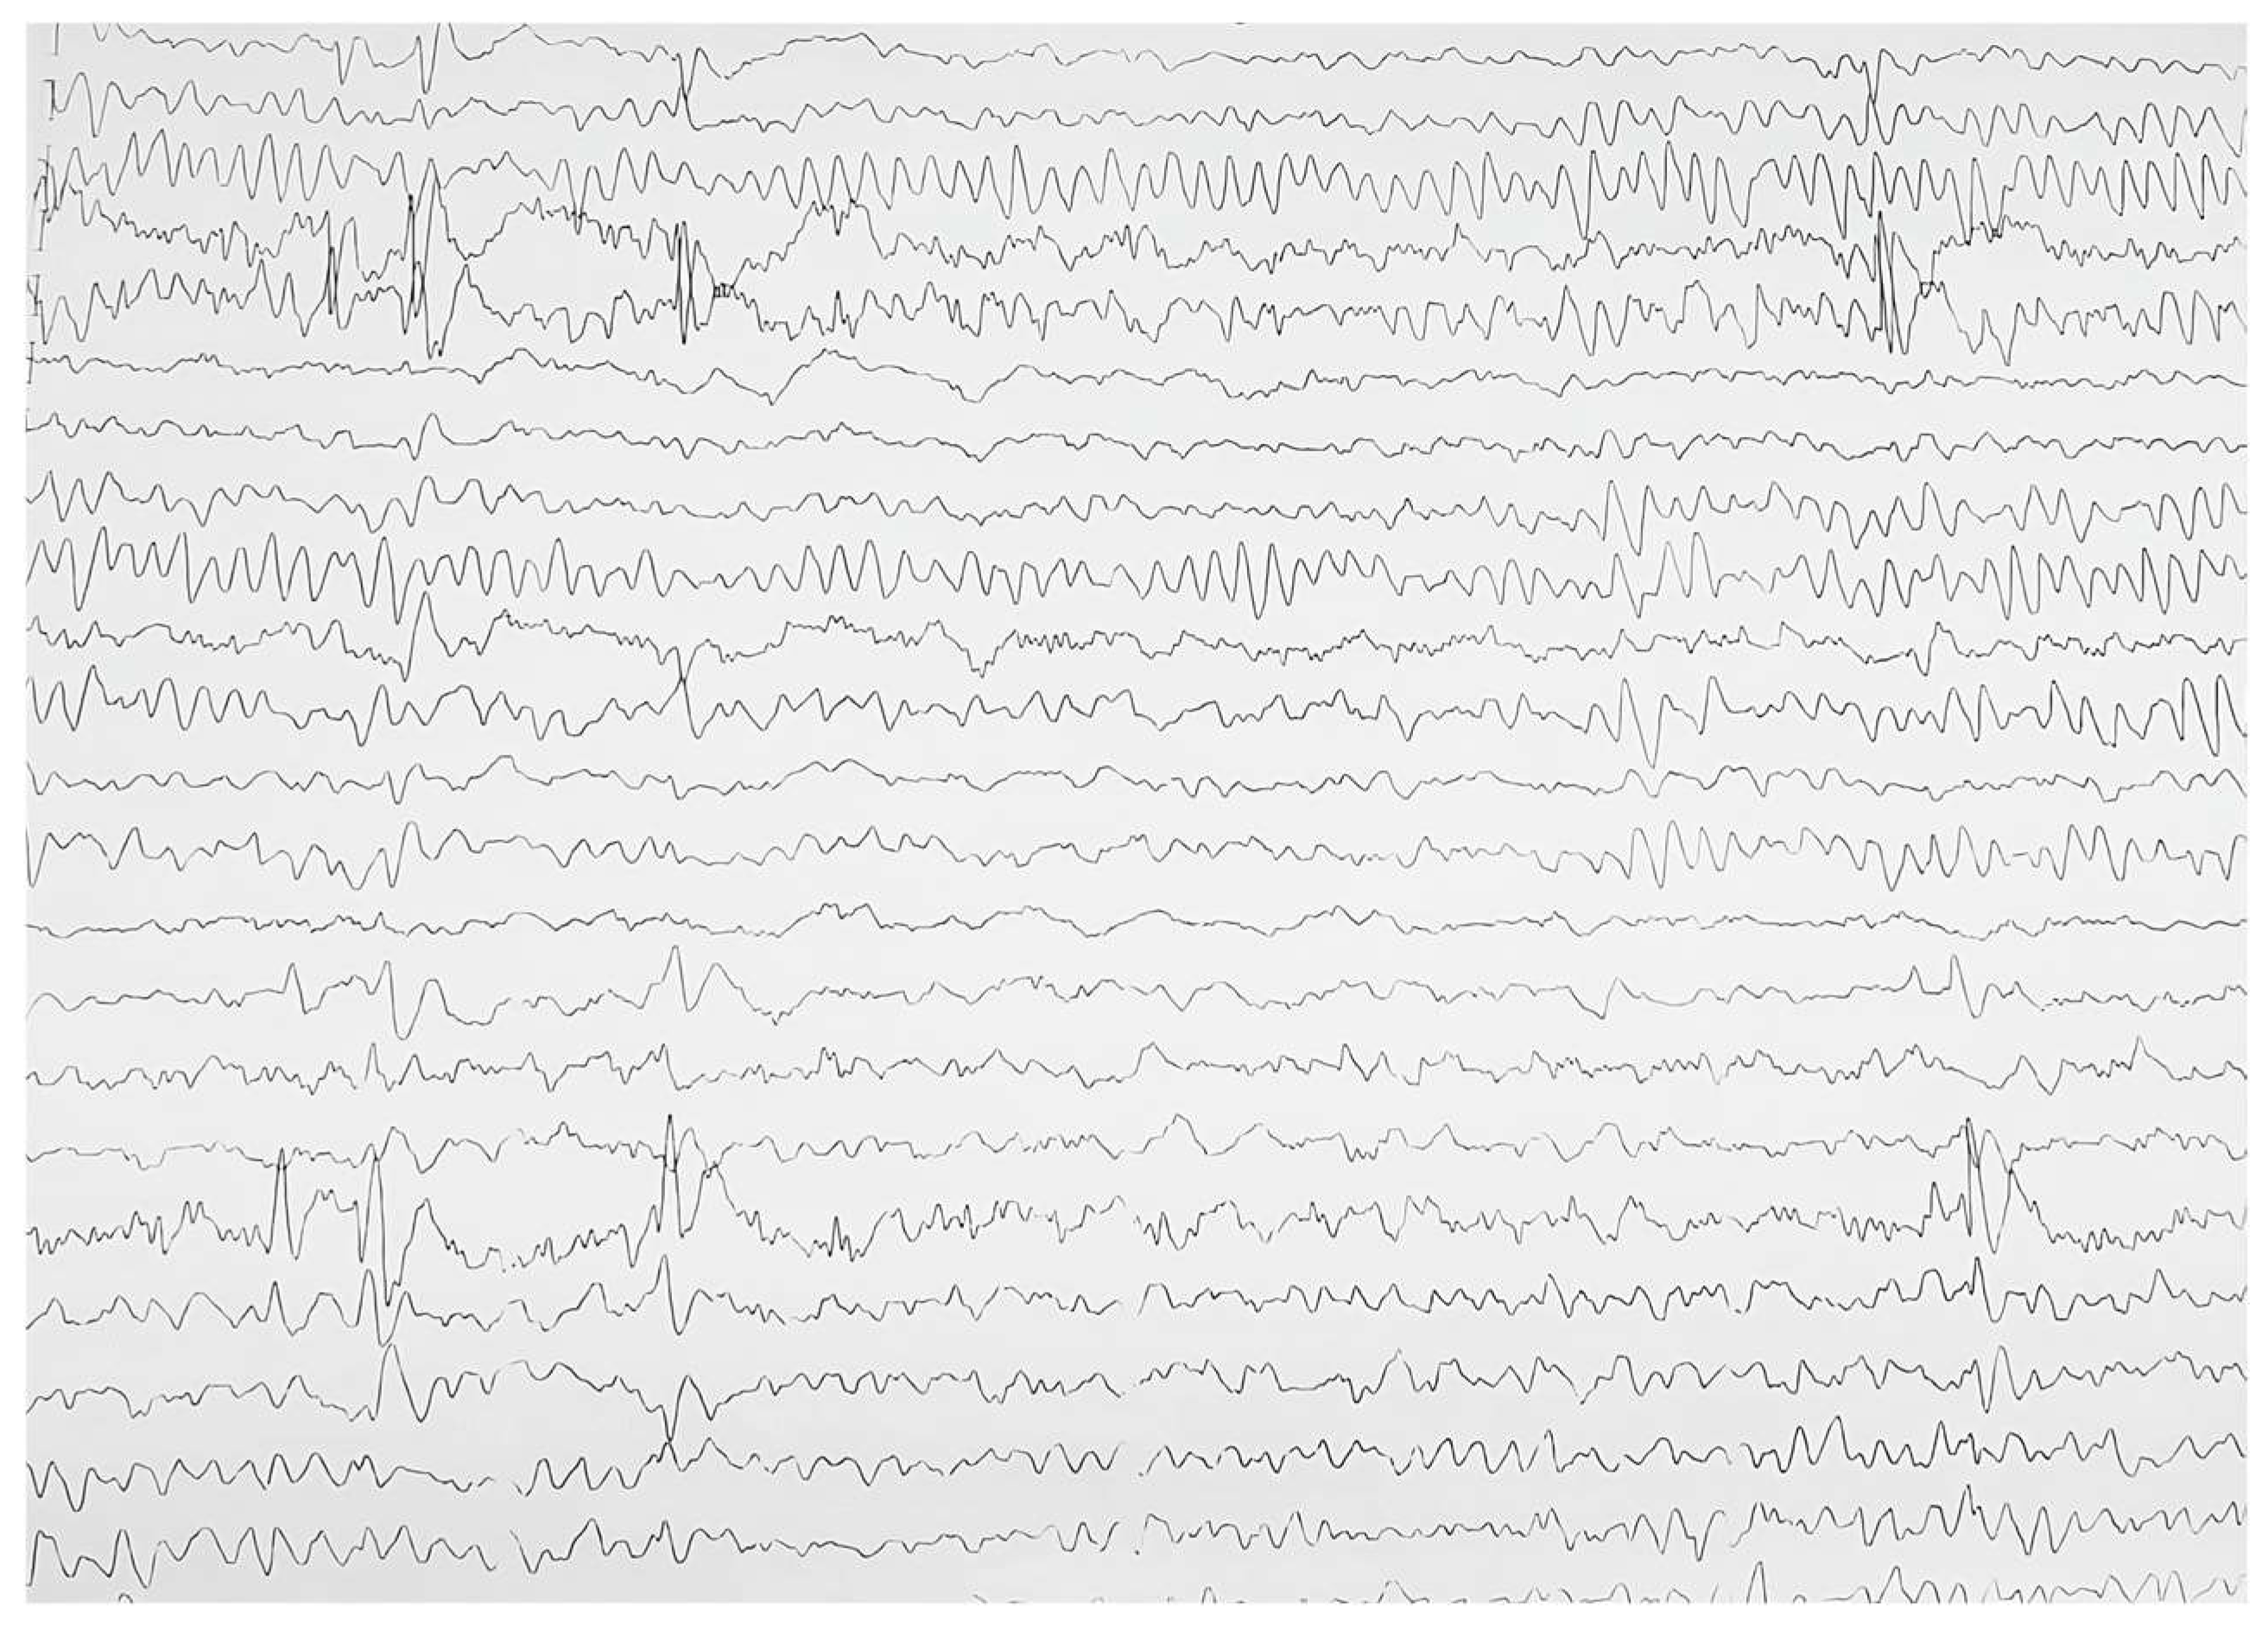

2.3. Biological and Paraclinical Assessment